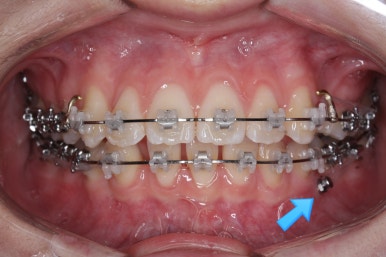

부산교정 키다리아저씨치과에서 결손치아 부분을 임플란트 하지 않고 치아교정을 통해서 개선한 이번 환자분의 치료를 마무리한 사진입니다.

치열은 가지런해졌고, 틈새는 없이 마무리되었습니다. 아랫니가 3개이지만 마치 4개인 것처럼 마무리하였고, 따라서 위~아래 치열의 중앙도 거의 맞게 마무리하였습니다.

(한 쪽은 송곳니를 앞니 대신 사용해야 했어서 크기 문제로 완벽히는 중앙을 맞추기 힘듭니다.)

아랫니를 살펴보면 화살표 표시를 해둔 송곳니~송곳니 사이에 치아가 1개 모자랍니다. 원래는 4개의 앞니가 있어야 하는데, 3개 밖에 없었습니다. 이런 결손치아의 경우는 다음과 같은 문제가 생깁니다.

결손치아 부위에 틈이 생깁니다.

결손치아 주위 치아들이 제대로 서있지 못하고 기울어지게 됩니다.

위-아래 짝이 맞지 않아 중앙선이라든지 교합에 문제가 생깁니다.

이번의 경우 앞니가 하나 없는 경우여서 위-아래 앞니가 앞뒤로 간격이 멀어지게 됩니다.